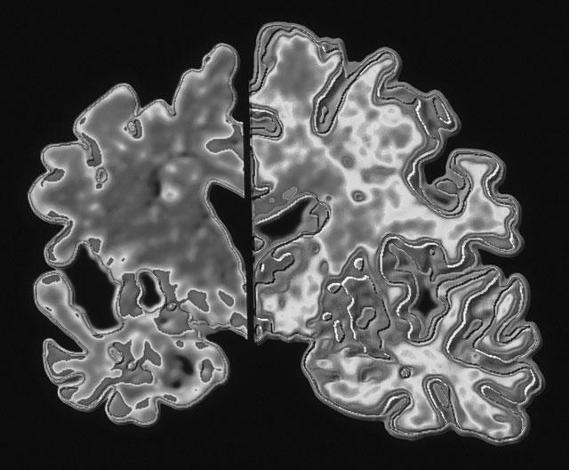

«Внучек, как фамилия того немца, по поводу которого я схожу с ума?» — «Альцгеймер, бабуля!» Этот бородатый анекдот уже никого не смешит. Ибо болезнь Альцгеймера превратилась в киллера XXI века, не щадящего ни президентов, ни премьер-министров, ни домохозяек. При этом ученые лишь приблизительно понимают причины развития недуга. Начинается болезнь незаметно, с кратковременных расстройств памяти, и заканчивается полной утратой этой функции. Сейчас недуг бьет в основном по пожилым людям, но с каждым годом болезнь молодеет. Сегодня на планете от нее страдают 35,6 миллиона человек, к 2050 году, по прогнозам Всемирной организации здравоохранения, если не предпринять ничего кардинального, число больных в мире достигнет 115 миллионов. Российские ученые, похоже, приблизились к пониманию того, как остановить распространение болезни Альцгеймера.

Эта болезнь не зависит от социального статуса, уровня достатка или отношения пациента к собственному здоровью. Маргарет Тэтчер, Рональд Рейган, Шон Коннери — они, как и миллионы других больных, не смогли ничего поделать с изменениями, пришедшими в их жизнь вместе с болезнью, поражающей нейроны головного мозга и приносящей потерю памяти, слабоумие, нарушение речи и прочие, порой самые неприятные симптомы. Клетки мозга, которые с рождения накапливали знания, отвечали за восприятие мира, определяли личность человека, в один момент вдруг начинают отмирать, оставляя несчастного наедине с неведомым ему окружением. «Порой больной человек не может надеть рубашку, потому что просто не знает, что нужно засунуть руки в рукава», — говорит невролог Московского областного научно-исследовательского клинического института имени М. Ф. Владимирского кандидат медицинских наук Ольга Штанг.

Как рассказал «Итогам» доктор биологических наук, ведущий научный сотрудник Научно-клинического центра геронтологии Минздрава РФ Александр Мальцев, «отсутствие методов лечения болезни Альцгеймера объясняется клиническими методами диагностики, которые выявляют заболевание на поздних стадиях, когда большая часть функциональных нейронов погибла». Фактически это признание того, что болезнь неизлечима. Однако в последние годы исследователи, работающие над лечением недуга, накопили данные о том, что он начинается задолго до того момента, когда появляются его первые клинические симптомы. Александр Мальцев утверждает: «Первичные молекулярно-дегенеративные процессы возникают у пациентов от 30 лет и позже. Далее патология развивается скрытно на протяжении длительного периода времени».

По разным данным, скрытая стадия может продолжаться от 5 до 25 лет, после чего начинается активная стадия, и она диагностируется клинически. Хотя именно тогда, когда большинство нейронов головного мозга еще дееспособны, возможно успешное лечение. Оказывается, все дело в ранней диагностике.

Кроме того, эксперименты и клинические наблюдения показывают, что болезнь провоцируют перегрузки нервной системы, к которой ведут стрессовые ситуации. То есть риск начала заболевания у активных молодых людей, живущих в городах, пытающихся ухватить и проанализировать каждый бит информационного потока, куда выше, чем у работяги, вытачивающего болванку от звонка до звонка. «Длительные упадки сил, потеря памяти, концентрации, непонятная затянувшаяся депрессия, хроническая усталость — все эти явления могут быть признаками начала болезни Альцгеймера», — подтверждает Ольга Штанг. Однако сегодня они считаются чуть ли не нормой для человека, живущего в городе. «Клинических же способов определить болезнь на ранней стадии нет», — продолжает врач. Вопрос в том, как же отделить зерна от плевел и не позволить себе к 60 годам потерять личность и стать обузой для родственников.